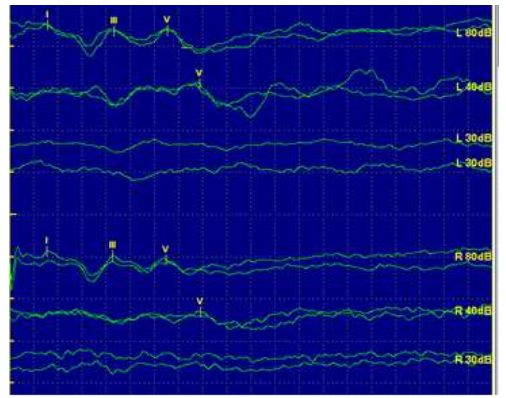

A avaliação eletrofisiológica da audição é bastante utilizada para inferir o limiar auditivo eletrofisiológico de

crianças que não respondem adequadamente à audiometria. Observe o traçado eletrofisiológico do PEATE-clique obtido abaixo, em que L se refere à (left) orelha esquerda e R se refere à (right) orelha direita.

Em relação a esse traçado eletrofisiológico, assinale a afirmativa correta.